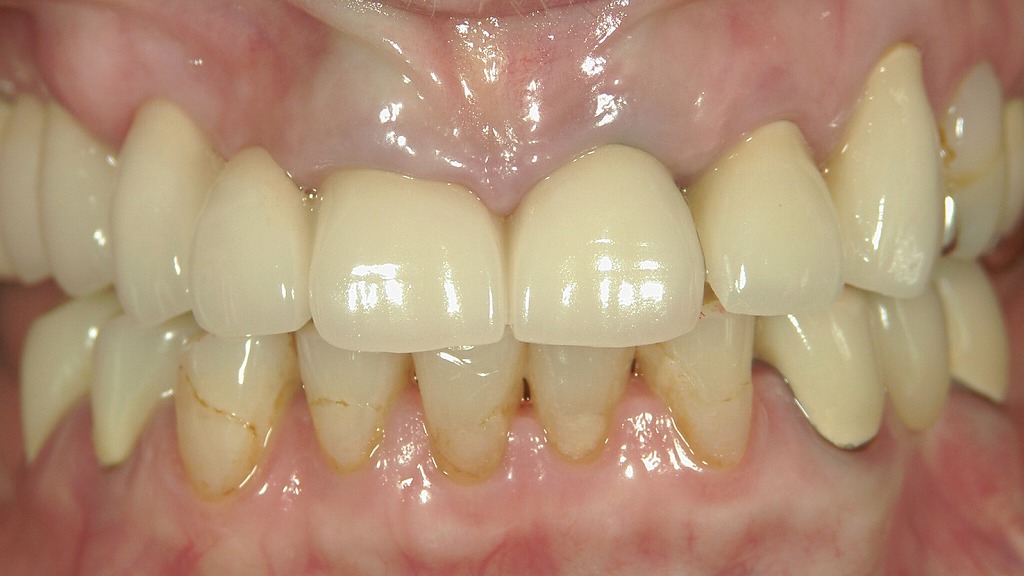

この画像は、前回のメタルボンドクラウン症例の術後1年経過時の状態を示しています。以下に詳細な解説を行います。

■ 左上1番の状態

前回、銀合金メタルコアによる**歯肉のメタルタトゥー(青黒い変色)**が見られた部分は、

ファイバーコアへ置換し、オールセラミッククラウンで補綴された結果、歯肉色は自然なピンクに近づいています。

わずかに変色が残存していますが、臨床的にはほぼ審美的に改善しています。

■ 補綴物の特徴

新たに装着されたクラウンは金属を使用しないオールセラミックであり、

透明感・光の透過性が天然歯に近く、周囲の歯肉との調和も良好です。

歯頚部ラインも滑らかで、歯肉との境界に黒変が見られません。

🦷 改善点のまとめ

| 改善項目 | 術前の状態 | 術後1年後の状態 |

|---|---|---|

| 歯肉の変色 | 明らかな青黒いメタルタトゥー | ごくわずかに残るがほぼ消失 |

| クラウンの色調 | 不自然な不透明感、金属縁の露出 | 天然歯に近い明るさと透明感 |

| 歯肉の健康状態 | 軽度の炎症・腫脹あり | 発赤消失、健康的な歯肉ライン |

| 審美性 | 金属の露出が目立つ | 自然で調和のとれた見た目 |

💡 臨床的考察

ファイバーコアとオールセラミックの組み合わせにより、

- 金属イオンによる歯肉変色が防止され、

- 歯肉との親和性が高まり、

- 長期的な審美性が維持しやすくなっています。

1年経過後の状態からみても、歯肉の安定性・補綴物の適合性は良好と判断されます。